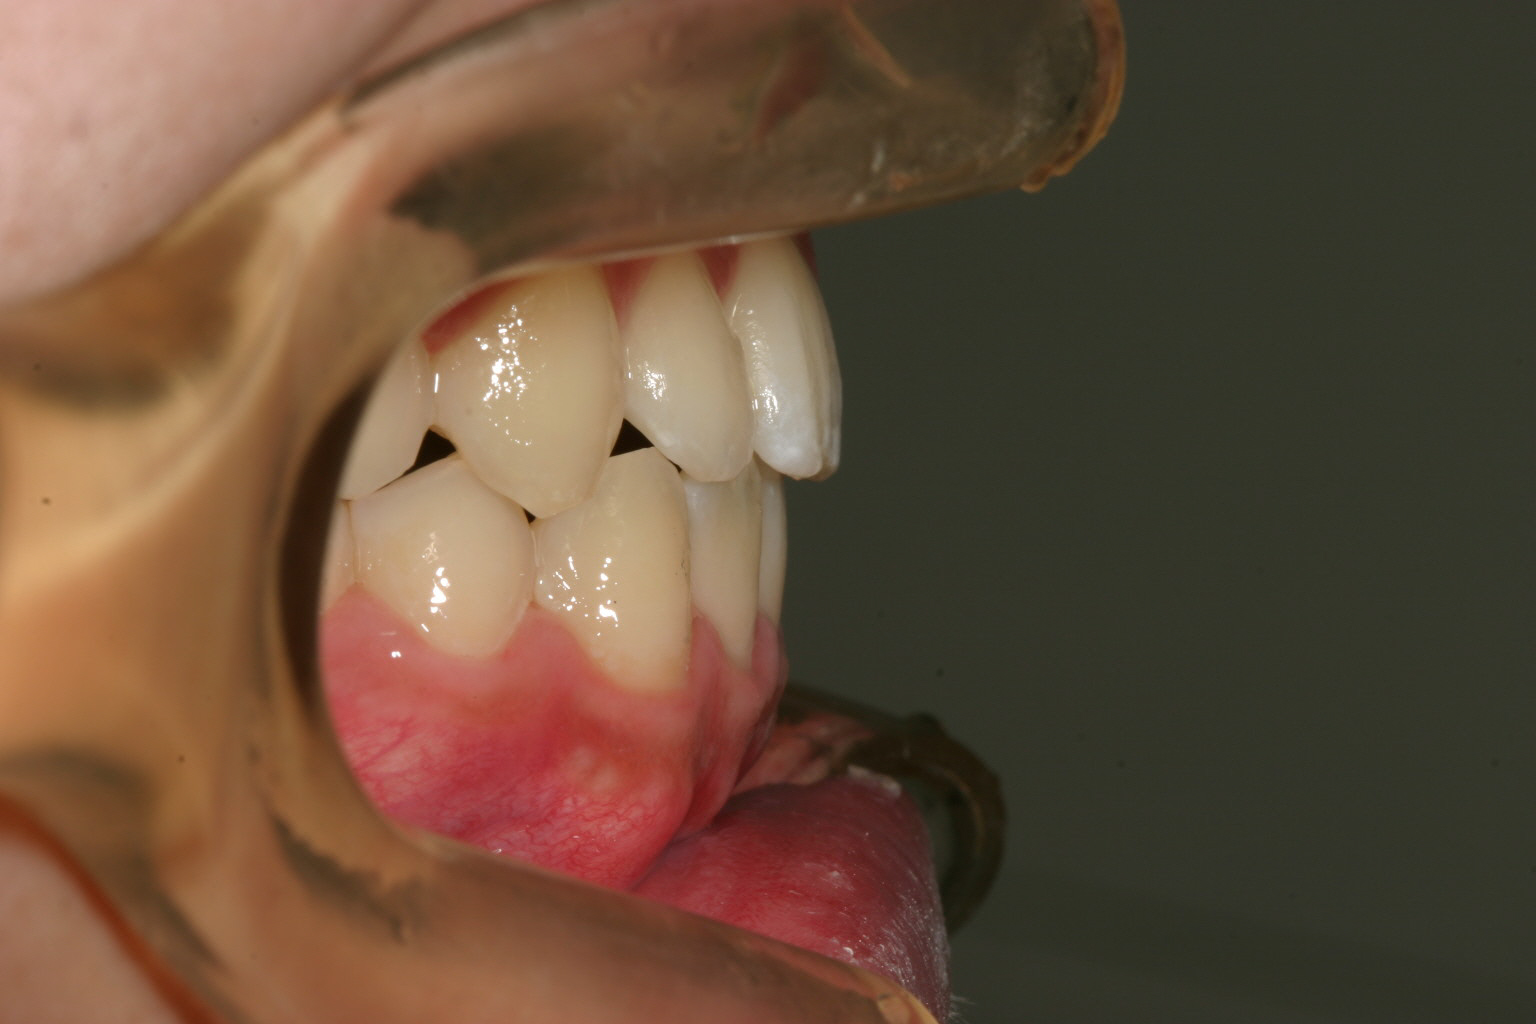

オーバージェットも綺麗に改善しています。

奥歯のかみ合わせを緊密にするためこの様なアップダウンエラスティックを使用しました。 その際も元々少ししゃくれ気味だったためCLASSⅢエラスティックとしています。

最終的に咬み合わせが少し甘いと感じた時はこの様なアップダウンエラスティックを使用致します。こうする事によりかみ合わせが緊密になります。